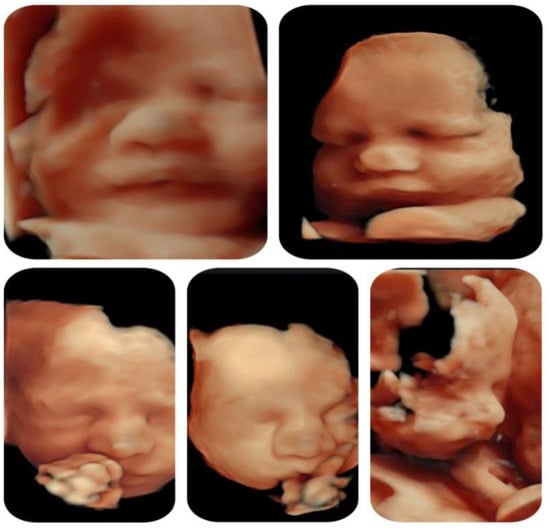

| Other ultrasonographic findings | Polyhydramnios Enlarged CSP Thymus hypoplasia Bulbous nose |